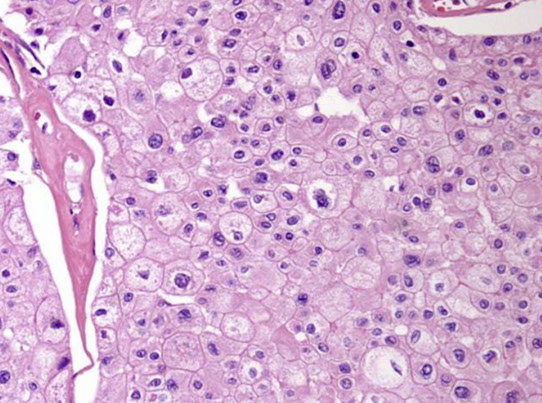

Collapsing Glomerulopathy

Assoc c HIV, blacks, IVDU, but can be 2/2 other causes (pamidronate tx), glomerular loops look like they have been sucked dry, c hypertrophy of glomerular epithelial cells that fill Bowman's space and separate collapsed glomerular tufts

On low power, has some abnormal tubules, which are dilated c casts, c inc cytoplasmic granularity

- glomeruli have collapse of capillary loops c vacuolated granular visceral epithelial cells on outside of collapsed tufts c material similar to tubular casts in Bowman's space

EM: tubulo-reticular bodies (agg of intracytoplasmic tubular structures in the ER)